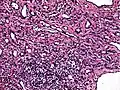

Low power photomicrograph of an endovascular papillary angioendothelioma showing papillae with hyalinized cores High power view showing a vascular tumor with cuboidal endothelium lining the vessels. Few entrapped seminiferous tubules are also noted (arrow).

High power view showing a vascular tumor with cuboidal endothelium lining the vessels. Few entrapped seminiferous tubules are also noted (arrow). Characteristic budding, hobnail-like endothelial cells visible.